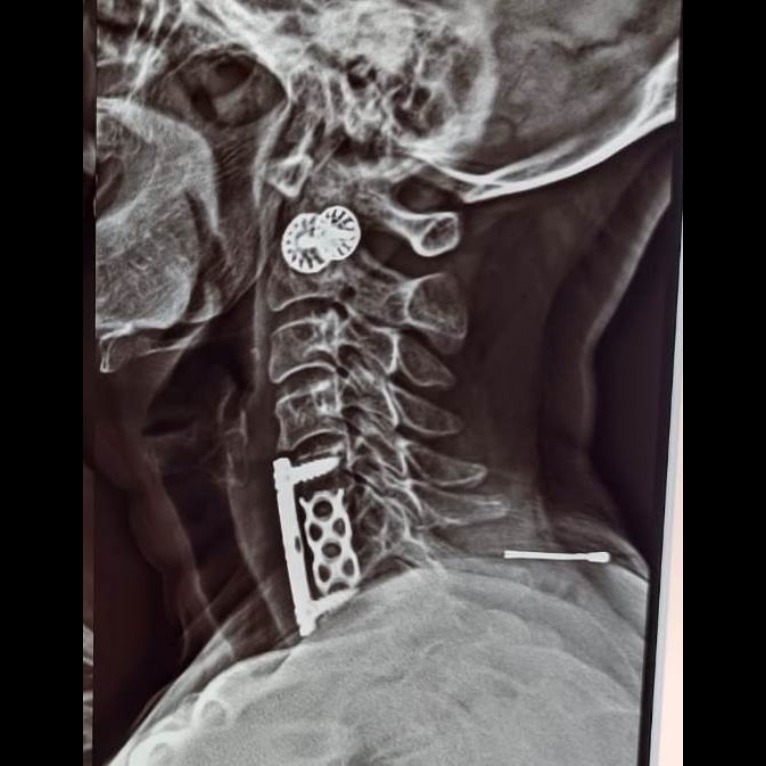

ANTERIOR CERVICAL SPINE FIXATION WITH DECOMPRESSION DISCECTOMY WITH INTERBODY CAGE WITH PLATTING - THIS SURGERY IS DONE IN FOLLOWING CONDITIONS :- *DEGENERATIVE DISC CONDITIONS IN CERVICAL SPINE *CERVICAL DISC PROLAPSE WITH NERVE ROOT COMPRESSION *CERVICAL CANAL STENOSIS *CERVICAL MYELOPATHY / CERVICAL CORD MYELOMALACIA *CERVICAL SPINE INFECTION *CERVICAL VERTEBRAL BODY FRACTURE ADVANTAGE :- *DONE THROUGH VERY SMALL HOLE BY USING ADVANCED MICROSCOPE – MAGNIFIED IMAGE OF NERVES, MUSCLES AND BLOOD VESSELS – SO NO CHANCE OF DAMAGE TO CRITICAL ORGANS *NO MUSCLE DAMAGE - ONLY MUSCLE RETRACTED *VERY LESS BLOOD LOSS *SMALL INCISION – COSMETIC GOOD *FAST RECOVERY *LESS INFECTION CHANCE *EARLY DISCHARGE FROM HOSPITAL